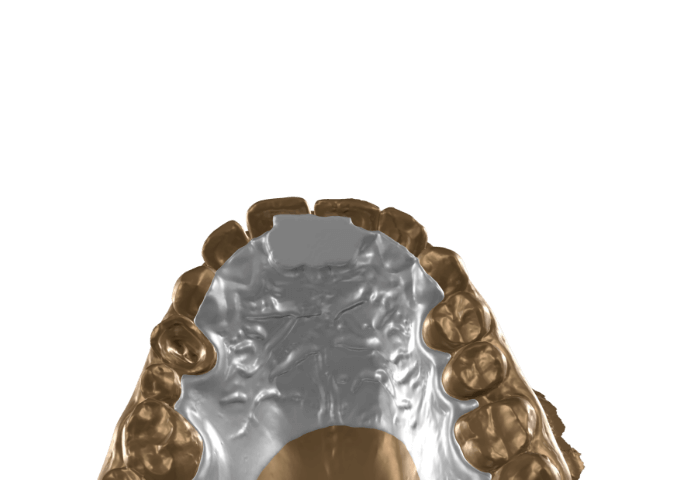

Blueprint

adds creative depth to your work

It lets you bring in scan data, CBCT, and motion

allowing you to extend your smile design into 3D.

It supports interdisciplinary spatial thinking and clear visual communication with your patient.

allowing you to extend your smile design into 3D.

It supports interdisciplinary spatial thinking and clear visual communication with your patient.

This technology is protected by Patent: NL 2037626